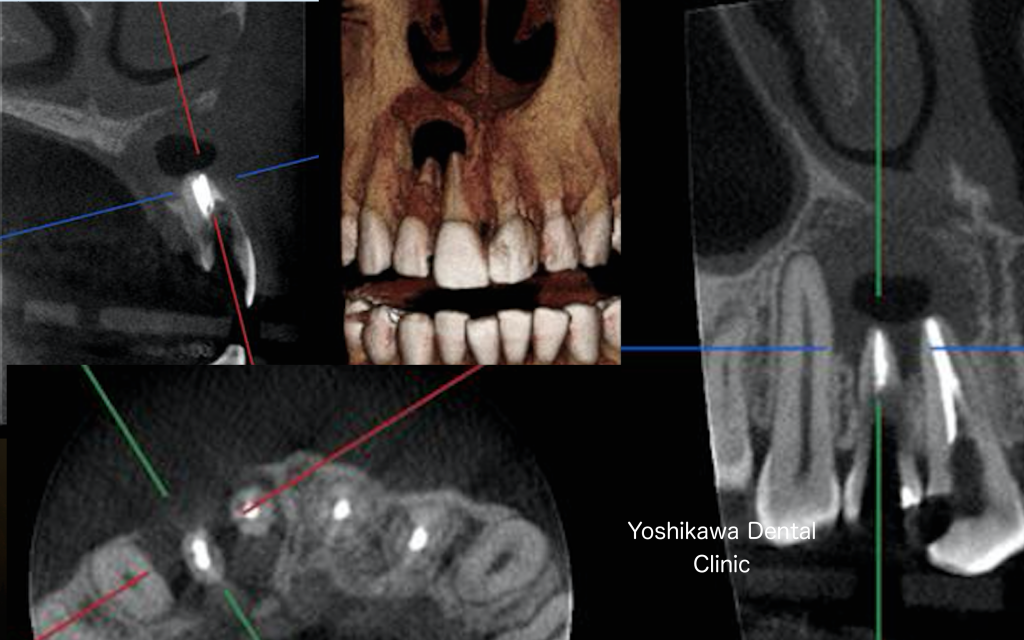

3Dの画像です。

やはり相当のダメージを負っています。根尖部の骨がピンポン玉くらいなくなっています。

体の内部に細菌が侵入すると必ず炎症反応が起こります。炎症反応とは体の防御反応なので細菌と白血球の戦いが局所で起こります。その結果白血球の死骸である膿が局所で溜まります。上のレントゲンでは炎症の結果、局所の骨がピンポン玉の大きさで失われました。

残念ながらこちらの患者さんは抜歯してブリッジという治療法を取るようになるでしょう。

抜歯をして原因が除去されれば骨は自然に再生されると思います。